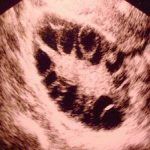

多囊卵巢综合症激素检查

女性激素高雄激素表现或/和FSH正常或偏低,LH升高,但无排卵前LH峰值出现。LH/FSH值>2(目前,大于1即可诊断)。LH/FSH比值升高多出现于非肥胖型患者,肥胖患者因瘦素等因素对中枢LH的抑制作用,LH/FSH比值也可在正常范围。如果是肥胖型患者还应该检测空腹血糖或OGTT试验,同时测胰岛素及甘油三酯等。